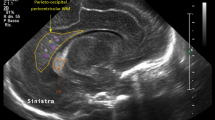

In the early 1980s it became possible to diagnose cystic WMI in preterm infants using CUS.35 De Vries et al. described a grading system for PVL that has been widely used:16 (I) transient periventricular densities (>7 days); (II) localized cysts besides the external angle of the lateral ventricle; (III) extensive cysts in fronto-parietal and occipital periventricular white matter (cystic PVL); (IV) extensive cysts in subcortical white matter (cystic subcortical leukomalacia). There is evidence of the correlation between this system and prognosis.36,37,38 However, several limitations are encountered when using the classification in clinical practice. Assessment of mild (grade I) WMI remains difficult because periventricular hyperechogenicity is a subjective finding. The interobserver agreement when interpreting hyperechogenicities has been remarkably low in some studies.39,40 As de Vries et al. point out, care should be taken not to overdiagnose transient hyperechogenicity.16 In general, echogenicity is considered pathological when it is equal to or greater than choroid plexus echogenicity. However, in extremely immature babies the use of this reference is questionable due to the more prominent and echoic choroid plexus in this population and also the fact that cystic PVL can be observed following flaring that never exceeded the brightness of the plexus (Fig. 2). CUS findings as regards periventricular hyperechogenicity that support grade I PVL include patchy appearance, extension of echogenicity beyond the peritrigonal area, and bilateral but asymmetric periventricular distribution.41 Homogeneous symmetrical hyperechogenicities are normal around the anterior frontal horns and the parieto-occipital junction of the lateral ventricles, representing the anterior limb of the internal capsule and the optic radiation, respectively.42,43

Maalouf, E. F. et al. Comparison of findings on cranial ultrasound and magnetic resonance imaging in preterm infants. Pediatrics 107, 719–727 (2001).

Mirmiran, M. et al. Neonatal brain magnetic resonance imaging before discharge is better than serial cranial ultrasound in predicting cerebral palsy in very low birth weight preterm infants. Pediatrics 114, 992–998 (2004).